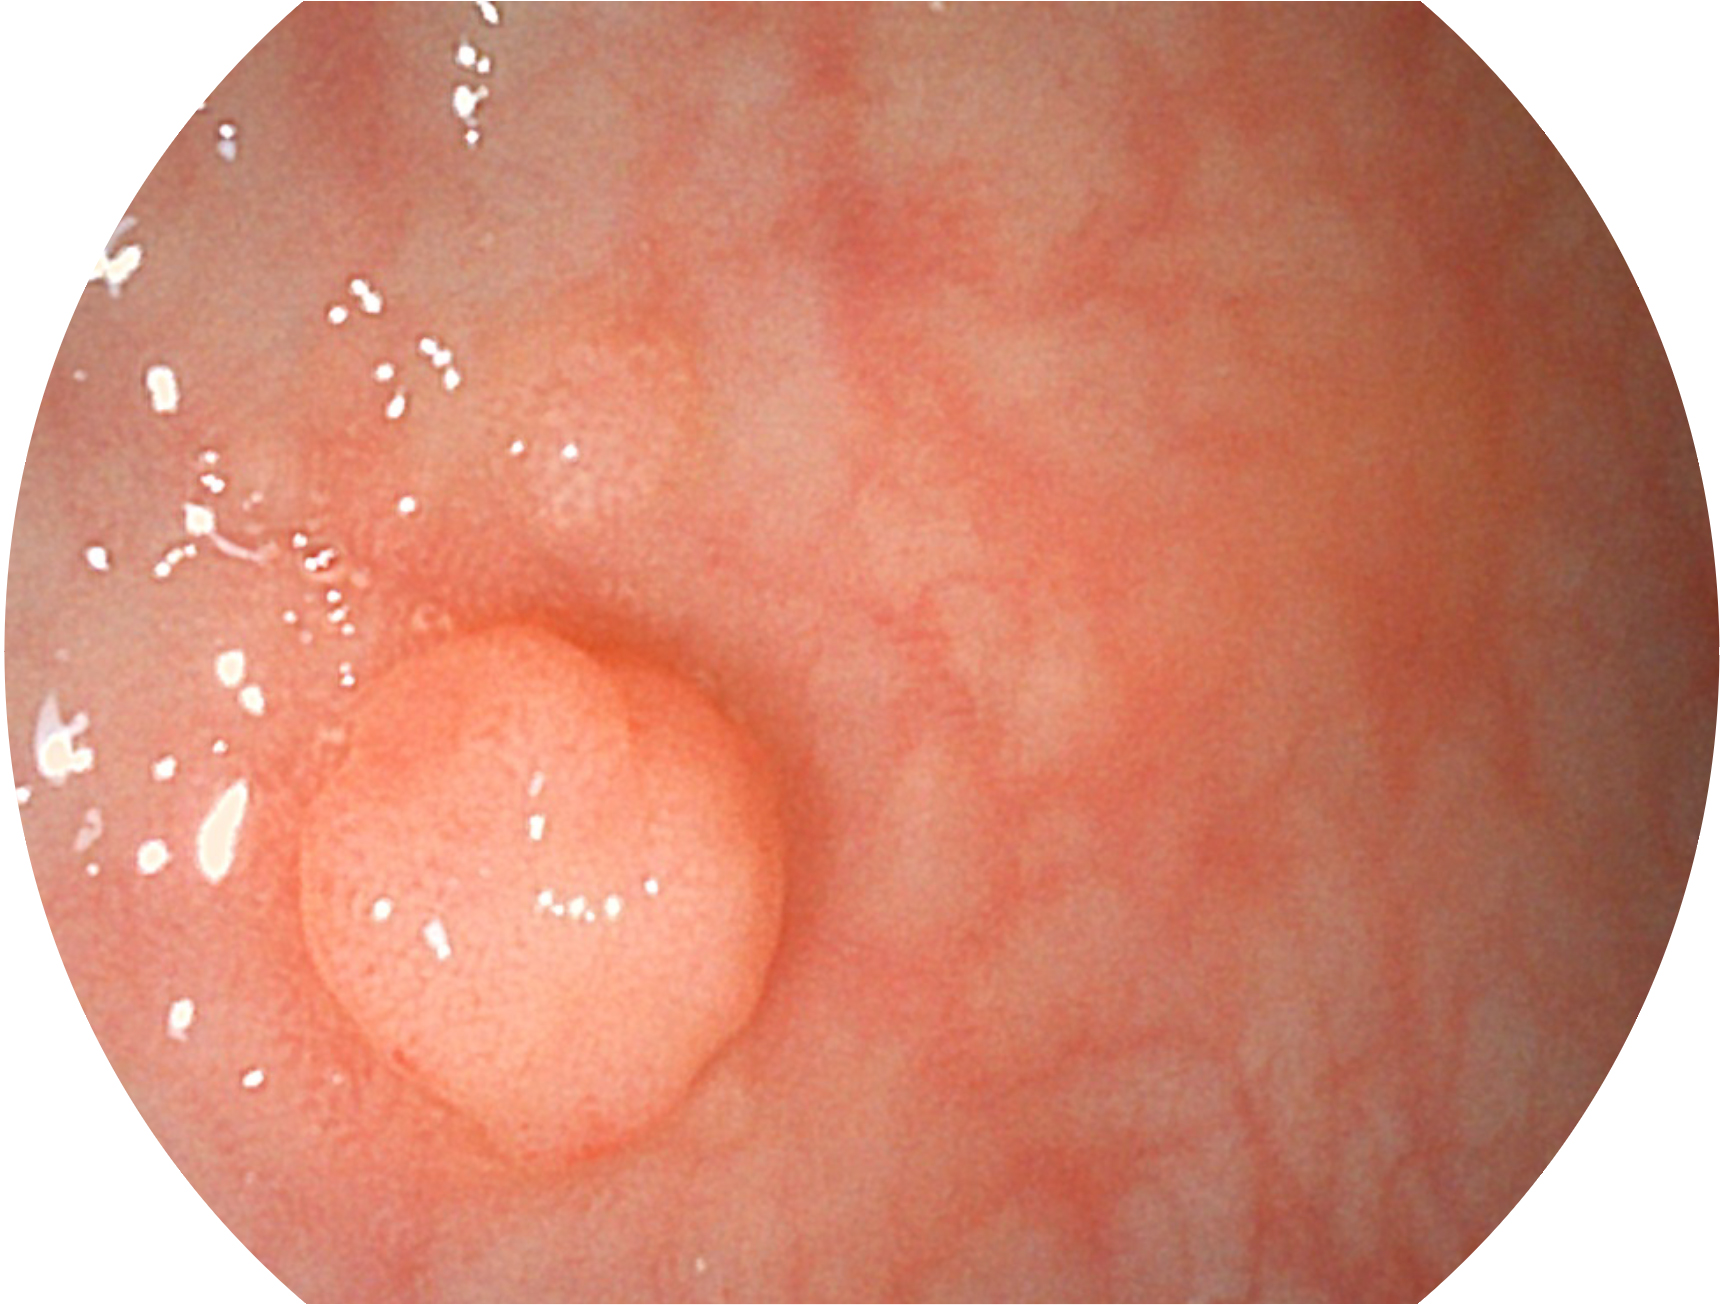

新葡的京集团8814检测站新开发的内镜染色技术,主要是基于多波长LED 光源的开发,VLS-55Q 四波长LED 光源是由四个不同颜色的LED光按照相应照明模式所规定的特定发光比例进行合束后形成,合束后形成的照明光的光谱由红光、绿光、蓝光及蓝紫光这四个不同的波段范围构成。具有更高光谱自由度,通过光谱比例的控制,实现了聚谱成像技术,英文全称为“Spectral Focused Imaging, SFI”,缩写为“SFI”和光电复合染色成像技术,英文全称为“Versatile Intelligent Staining Technology, VIST”,缩写为“VIST”。